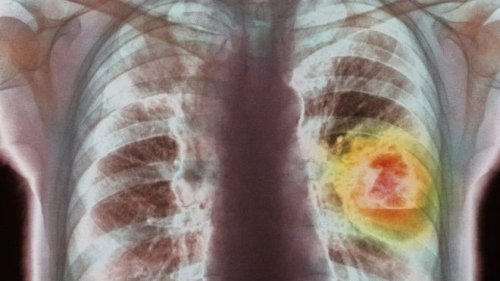

英国的国民保健系统(NHS)医院即将进行肺癌呼气检测的临床试验。

剑桥大学的一家分支公司“欧尔斯通”开发的这台“肺癌显示检测器”用于检查呼气中的化学物质,从而显示患者是否可能患有肺癌。该公司的一名创办人比利·博伊尔说,这台手提器材可能在两年内提供给家庭医生使用。

他希望有关科技可以尽早诊断出患者的肺癌情况。在英国每年有3万5千多人死于肺癌,存活率很低,原因是很多病例诊断出的时候已经属于末期癌症。